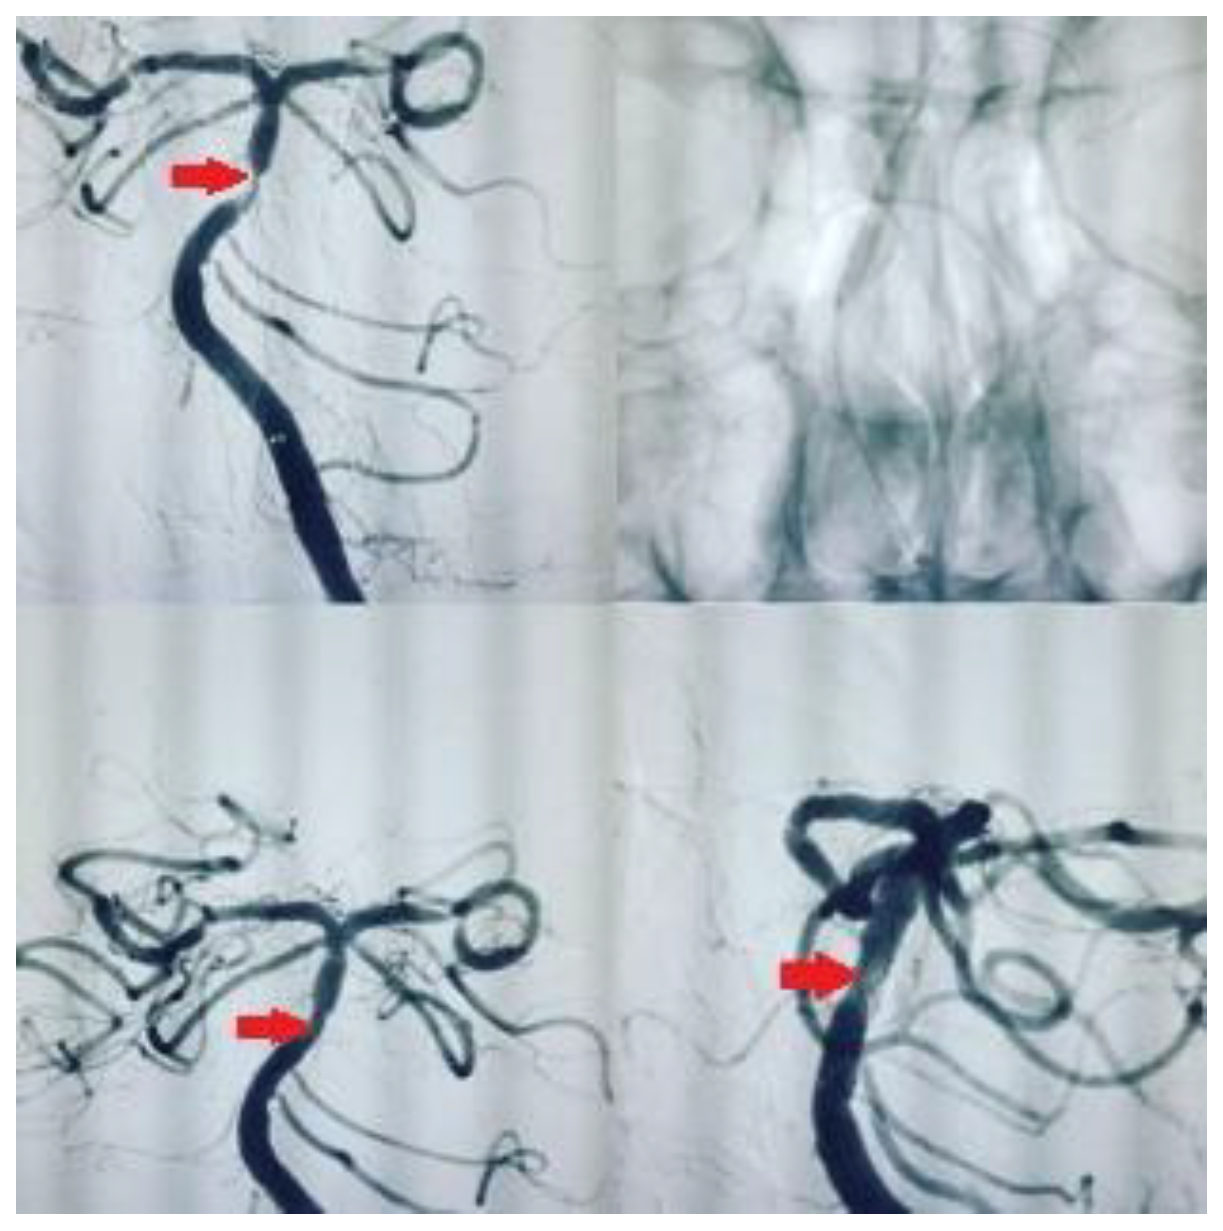

We used self-expanding stents (Enterprise® stent or ACCLINO® flex plus Stent). The responsible physician selected those stents, which were the best fit for each patient. Angiography was performed with an interventional system (Siemens Axiom Artis zee 2011; Siemens Healthcare, Erlangen, Germany), and predilatation with a balloon was performed in most patients. Examples of stenting in our patients are shown in Figure 1 and Figure 2. We used the Thrombolysis in Cerebral Infarction (TICI) scale to assess the degree of reperfusion following intracranial stenting. It classifies blood flow restoration into five categories based on angiographic findings. TICI 0 represents no perfusion, indicating complete occlusion with no distal flow. TICI 1 signifies minimal perfusion, where some contrast passes beyond the occlusion but without significant tissue perfusion. TICI 2a refers to less than 50% reperfusion of the affected vascular territory, whereas TICI 2b indicates more than 50% but incomplete reperfusion. The highest grade, TICI 3, reflects full perfusion, where the treated vessel achieves complete restoration of blood flow. We accepted TICI 2b–3 as successful revascularization, as it correlates with better functional outcomes and reduced long-term disability.

Figure 1. Symptomatic atherosclerotic stenosis in the basilar artery in a 60-year-old male patient, with a history of smoking, type 2 diabetes mellitus, and hypertension, was treated with elective intracranial stenting.